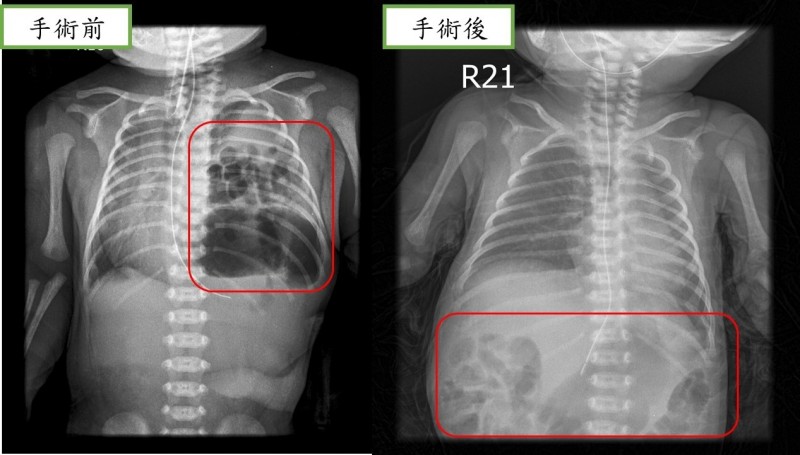

近日,重醫附屬兒童醫院心胸外科醫護團隊為這名男孩進行了手術,幫他將腸道送回腹腔,再補好了腹腔和胸腔中間膈肌的殘缺。手術順利完成。醫師提醒,孕產婦孕期一定按時要做好產檢,先天性膈疝最早可以在孕12周左右做產檢時通過彩超發現,如果孕期診斷,還應與其他畸形進行鑒別,同時根據多個指標評估胎兒膈疝病情的輕重,決定進一步處置方案。

孕期診斷後,要選擇合適的生產醫院,出生后及時轉運至有救治能力的專科醫院,依據病情嚴重程度和臨床表現決定手術時機,該疾病一旦診斷,原則上均需要儘早手術治療,減少對孩子的影響。